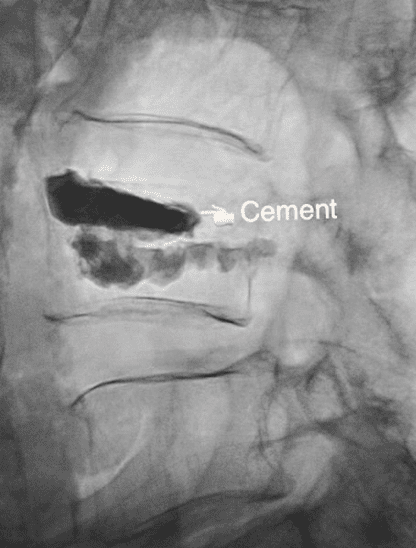

- Bone cement is then inserted through the needle into the fractured bone

- Once the cement is carefully placed, everything is removed and the cement will harden in minutes